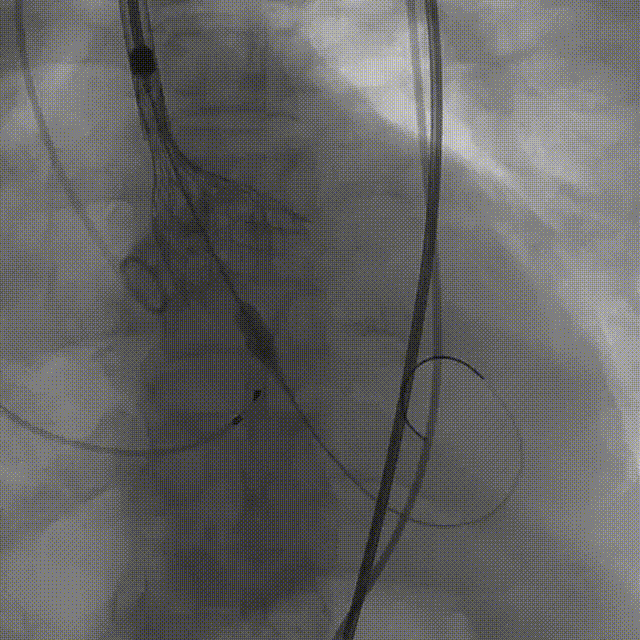

输送器柔顺过弓、跨瓣

瓣膜开始零位定位

瓣膜逐步释放到工作位

工作位造影位置良好

瓣膜逐个脱钩